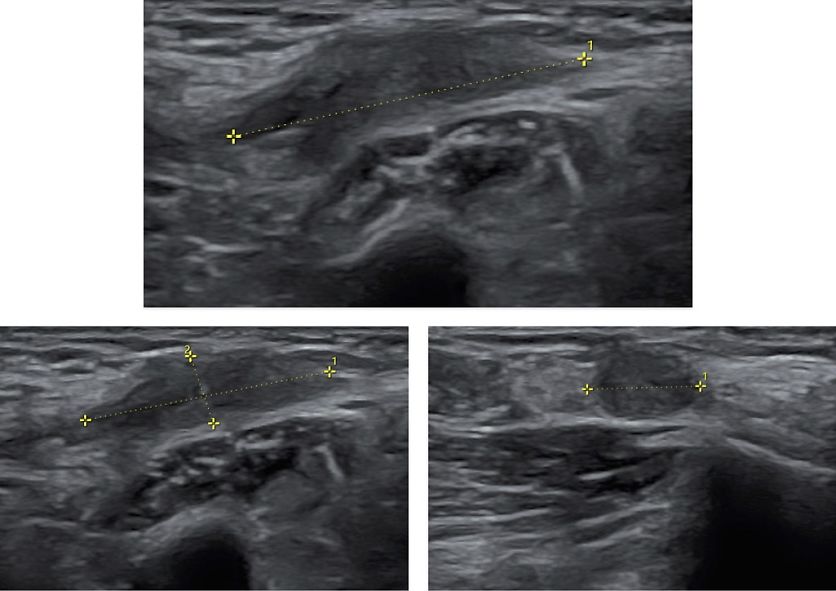

Ureters

Ureteral endometriosis (UE) is classified as extrinsic (fibrotic compression) or intrinsic (intraluminal infiltration), with extrinsic being more common.5 Although UE may be asymptomatic, it carries the risk of progressive hydronephrosis and renal damage. TVS can indirectly identify UE through visualization of hydronephrosis or ureteral dilatation (> 6 mm) and directly as a hypoechoic band or nodule compressing or deviating the distal ureter34 (Figure 13, Video 2).

The distal ureters can be identified laterally and posteriorly to the uterine arteries in the longitudinal plane. Deviation, thickening or reduced mobility of the ureter at this level should raise suspicion of UE involvement. Assessment of ureteral jets with color Doppler is recommended to confirm ureteral patency. In cases of hydronephrosis or loss of ureteric visualization, further imaging, such as renal ultrasound (Figure 14), computed tomography (CT) scan or MRI scan, should be considered.32

Both ureters and kidneys should be systematically evaluated in all patients with DE, particularly when sacrouterine ligament (SUL) or parametrial nodules are present. Ureteral involvement is often underestimated yet has significant surgical and functional implications.33,35

13

Parametrial fibrosis causing distal ureteral stenosis with proximal dilatation.

14

Renal assessment is an essential part of the endometriosis ultrasound protocol. Up to 3% of patients present with silent hydroureteronephrosis.